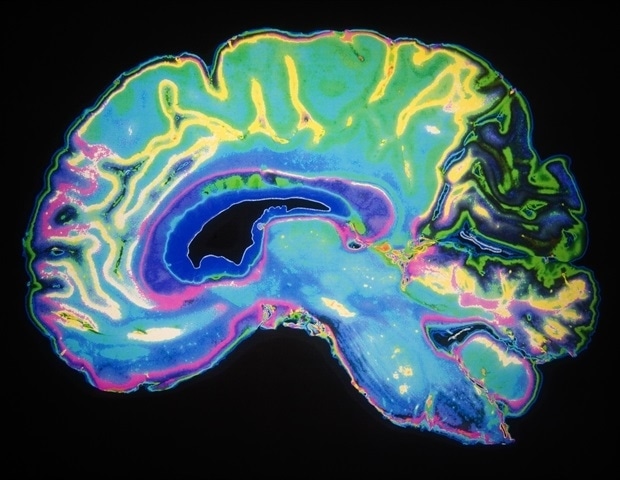

GPT-4 מראה הבטחה באיתור נגעים במוח לאחר שבץ מוחי

בינה מלאכותית (AI) עשויה לשמש כלי עתידי לנוירולוגים כדי לסייע באיתור היכן במוח התרחש שבץ מוחי. במחקר חדש, AI עיבד

בינה מלאכותית (AI) עשויה לשמש כלי עתידי לנוירולוגים כדי לסייע באיתור היכן במוח התרחש שבץ מוחי. במחקר חדש, AI עיבד

דרך חדשה להדמיית המוח באמצעות הדמיית תהודה מגנטית (MRI) אינה מזהה ישירות פעילות עצבית כפי שדווח במקור, על פי מדענים